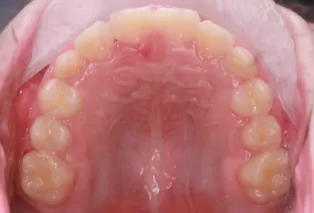

Intraoral photos